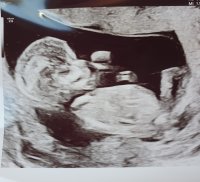

Alt ser fint ut, og jeg ble satt frem 8 dager til 12+5, fikk også en video av en liten sprellende baby:Heartred